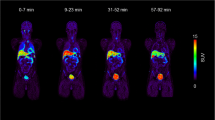

In average, (2.4 ± 0.1) MBq per kg bodyweight (range: 2.3–2.5 MBq/kg) were injected. Organs showed in general low uptakes, see Fig. 2a, while the renal cortices were clearly visible with a SUV of in average (8.6 ± 2.3) after 30 min (average of all left and right kidneys), which slowly dropped over time until a SUV of (1.3 ± 0.2) after the full examination time of 270 min. All according time activity curves including heart are presented in Fig. 2b.

Dynamic series of static images of [18F]Me4FDG. a: dynamic series of static images of [18F]Me4FDG showing the biodistribution of this tracer. The first image represents a sum of the first 30 min. b: dynamic uptake behavior, with the renal parenchyma showing the highest uptake at the beginning of the tracer injection. Mean SUV of all referring regions is shown. SUV: standardized uptake value